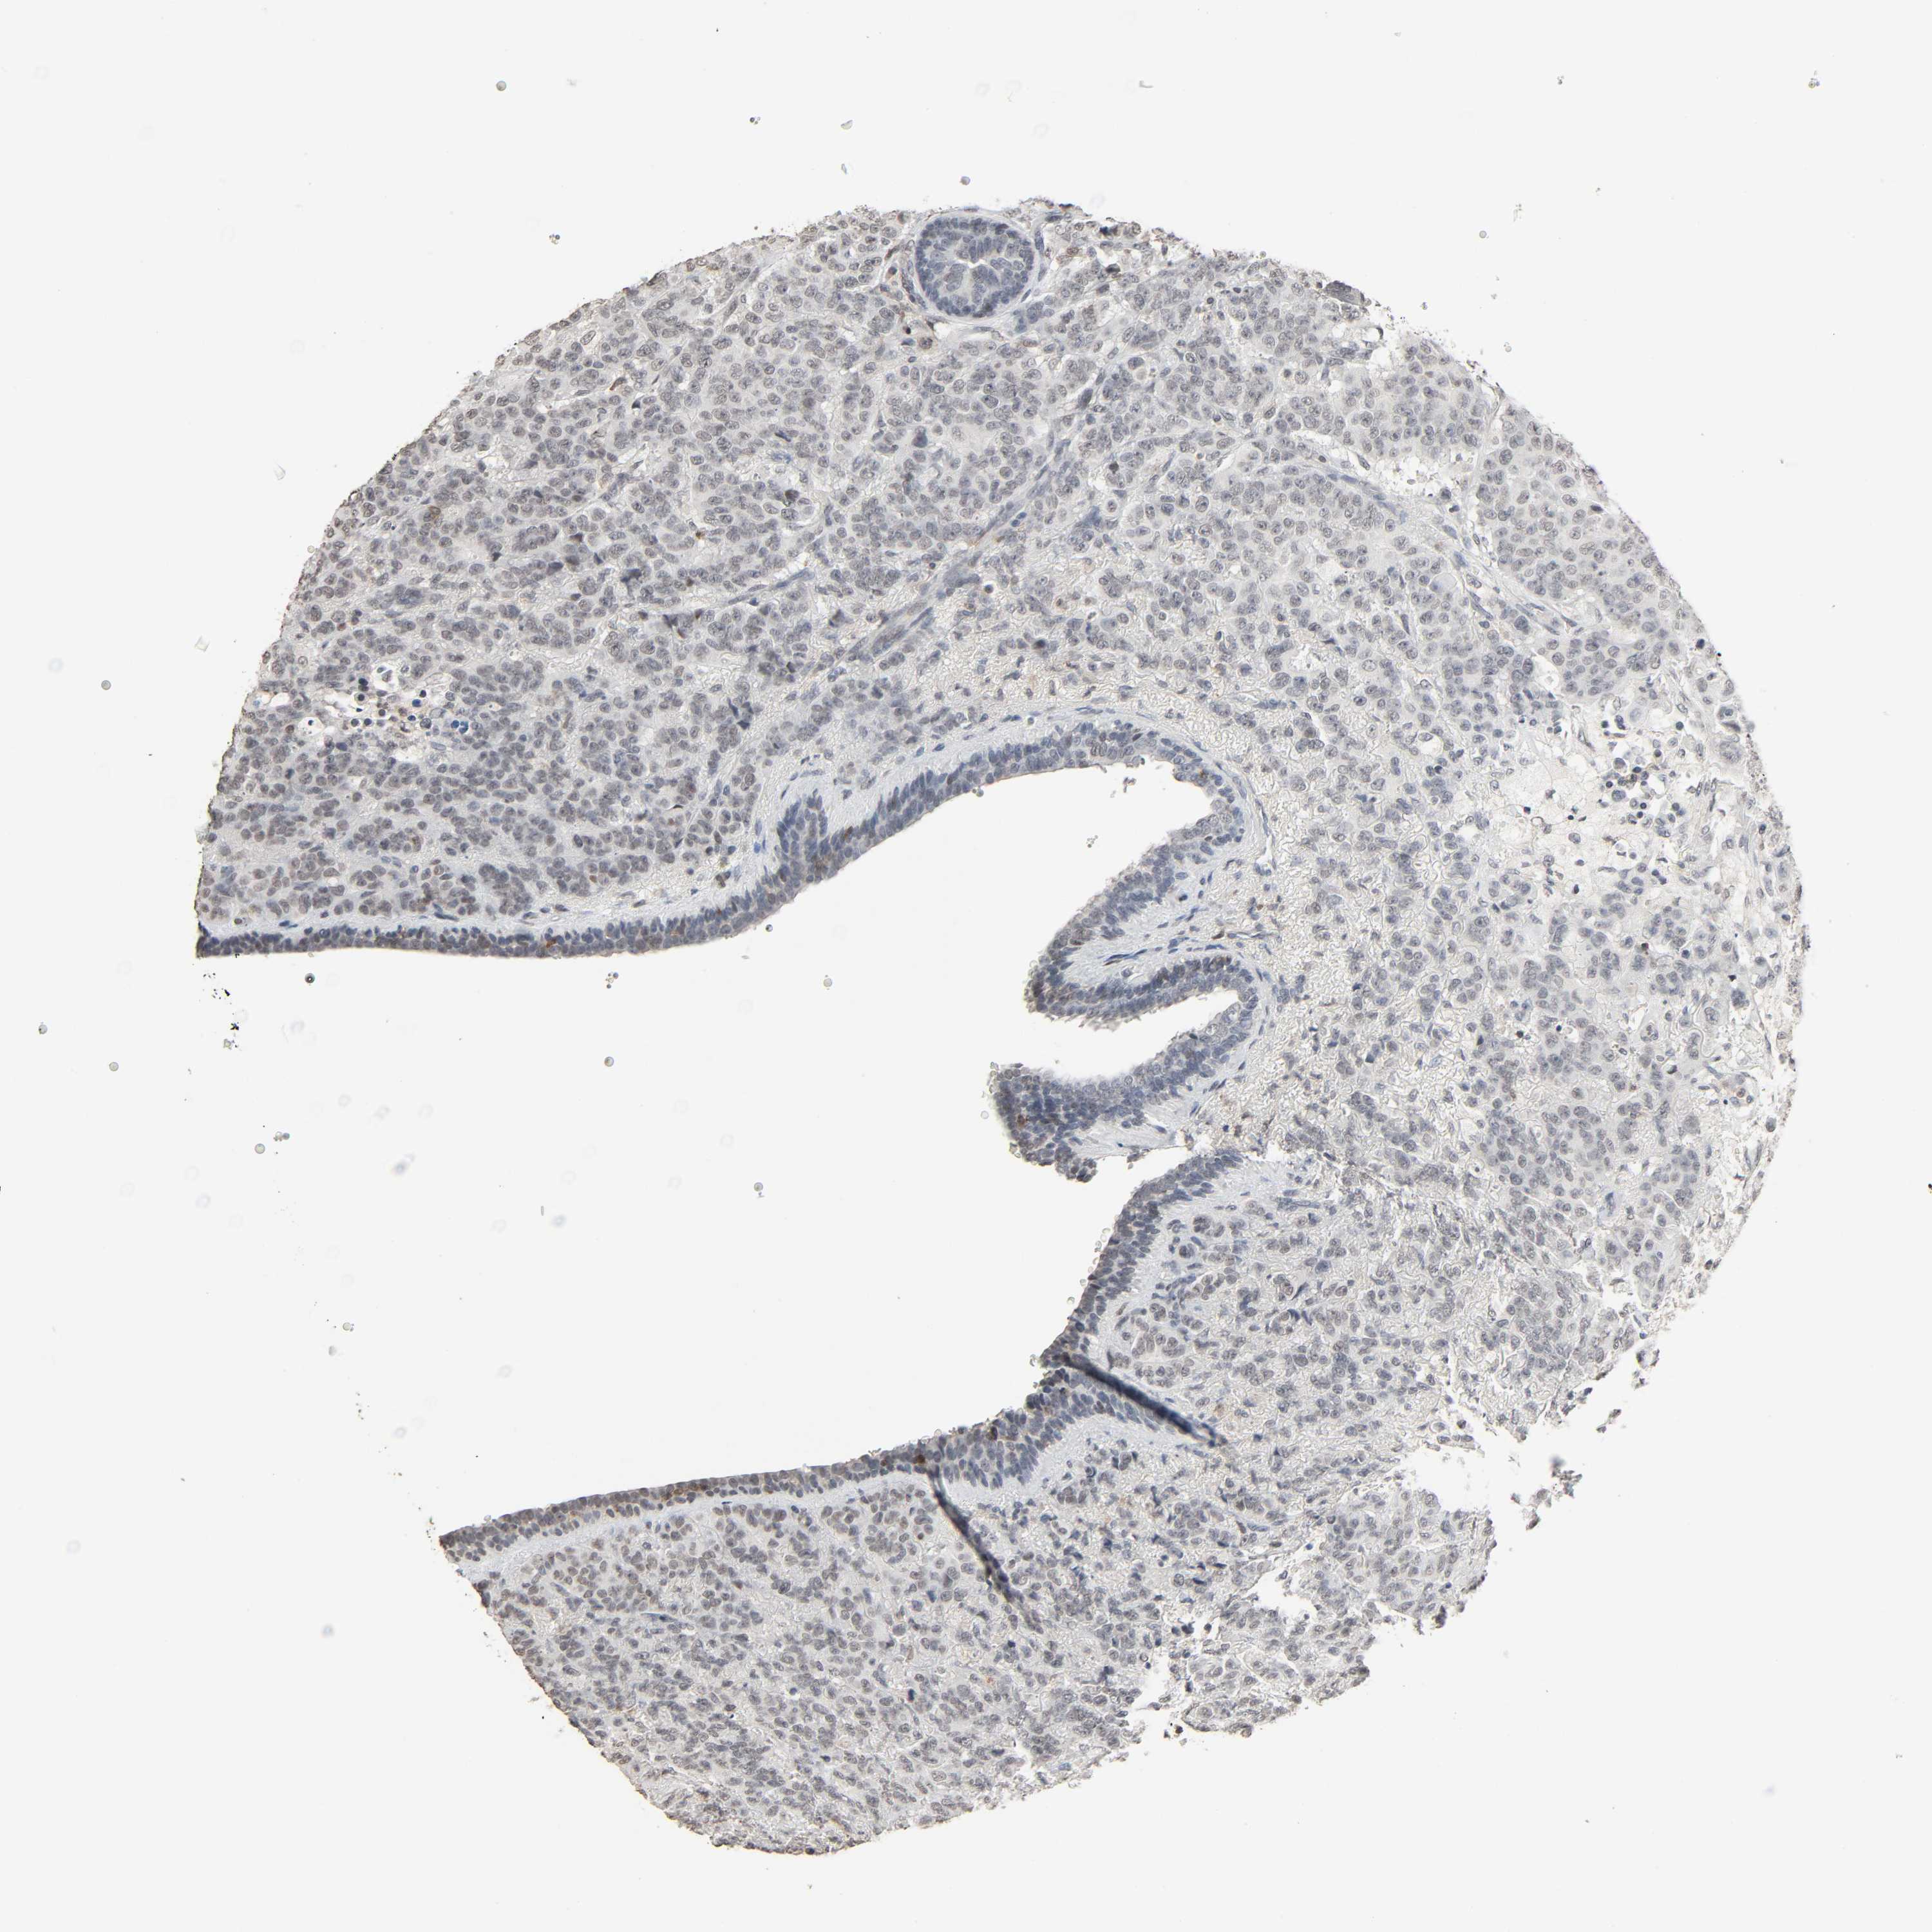

BRCA TCGA BRCA VALIDATION PROTEIN EXPRESSION